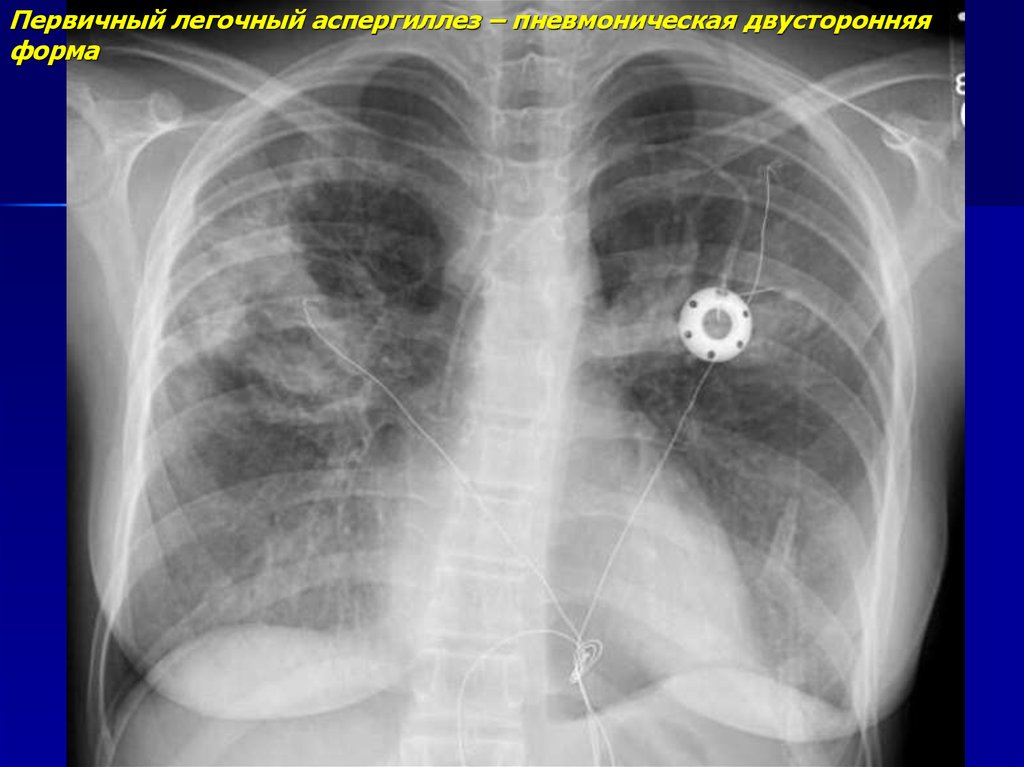

Визуализация и диагностика неинвазивного аспергиллеза с помощью КТ

Раздел: Необычные решения